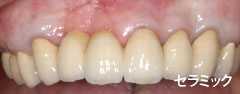

| 歯茎にプラーク(歯垢着が)と歯石の沈認められます。歯肉が腫れ、出血がありました。 | 歯科衛生士の治療と、ブラッシング技術の向上により、歯茎が引き締まり健康的な状態になりました。 | |